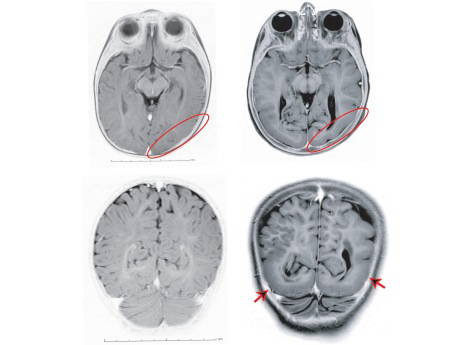

İlk yapılan incelemelerde hastanın beyninin büyük bir kısmının normal geliştiği halde, görme merkezlerinin bulunduğu arka kısmının kıvrımlarının oluşmadığı, beyin yüzeyinin düz kaldığının görüldüğünü belirten Günel, hasta üzerindeki ilk genetik incelemelerin 6 senedir çalışmalarını beraber yürüttüğü Dr. Kaya Bilguvar'ın gözetimi altında, İstanbul Üniversitesi Tip Fakultesi öğrencisi Tanyeri Barak tarafından başlatıldığını belirtti.

''Yapılan ileri biyolojik çalışmalar, 'laminin-gamma3 (LAMC3)' isimli bu genin beynin gelişimi sırasında kök hücrelerce sentez edildiğini ve daha ileri dönemlerde beyindeki sinir hücrelerinin birbiri ile temaslarını sağladığı gösterdi. Detaylı radyolojik incelemeler Acıbadem Üniversitesinde Prof. Alp Dinçer tarafından yapıldı. Saliha Yılmaz, Mehmet Bakırcıoğlu, Ahmet Okay Çağlayan ve Ali Kemal Öztürk çalışmada yer alan diğer Türk araştırmacılar oldu.

İnsan beyninin gelişiminde çok temel bir rol oynayan bu genin keşfi, insanların en üstün yapısı olan beynin sırrını anlamaya bizi bir adım daha yaklaştırmış oldu. İnsan beynindeki kıvrımlar, beynin en üst tabakasının yüzey alanını genişletiyor ve bir anlamda beynin kompütasyon gücünü arttırarak kompleks işlemleri yapmasına olanak sağlıyor. Beynin oluşumunda önemli rol oynayan bu genlerin keşfi, önleyici hekimlik hizmetleri sayesinde bu tip hastalıkların engellenmesi ve hem bu hastalıkların, hem de beyni geç yaşlarda etkileyen Alzheimer ve Parkinson gibi hastalıkların ilerideki tedavilerine zemin hazırladığı için büyük önem taşıyor.''